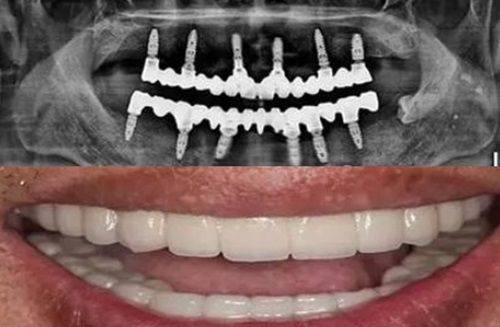

打桩并不是所有根管治疗后的大牙都需要的步骤,是否需要打桩取决于剩余牙体组织的量。当大牙因为龋坏、外伤等原因,导致牙冠剩余的健康牙体组织较少(通常超过1/2的牙体缺损)时,直接佩戴牙冠的话,牙冠的固位力不足,特别容易出现脱落,此时就需要在根管内打入桩核,比如纤维桩、金属桩,以此增加牙体的整体强度和固位能力,让牙冠可以更稳固地附着在牙齿上。

如果剩余的牙体组织足够多,能够为牙冠提供足够的固位力,就不需要打桩,直接制作佩戴牙冠即可。医生会在根管治疗完成后,通过口腔检查、X光片等方式评估剩余牙体组织的量,判断是否需要打桩。需要注意的是,打桩的操作需要严格规范,避免损伤根管周围的组织,否则可能会影响牙齿的长期使用成效。